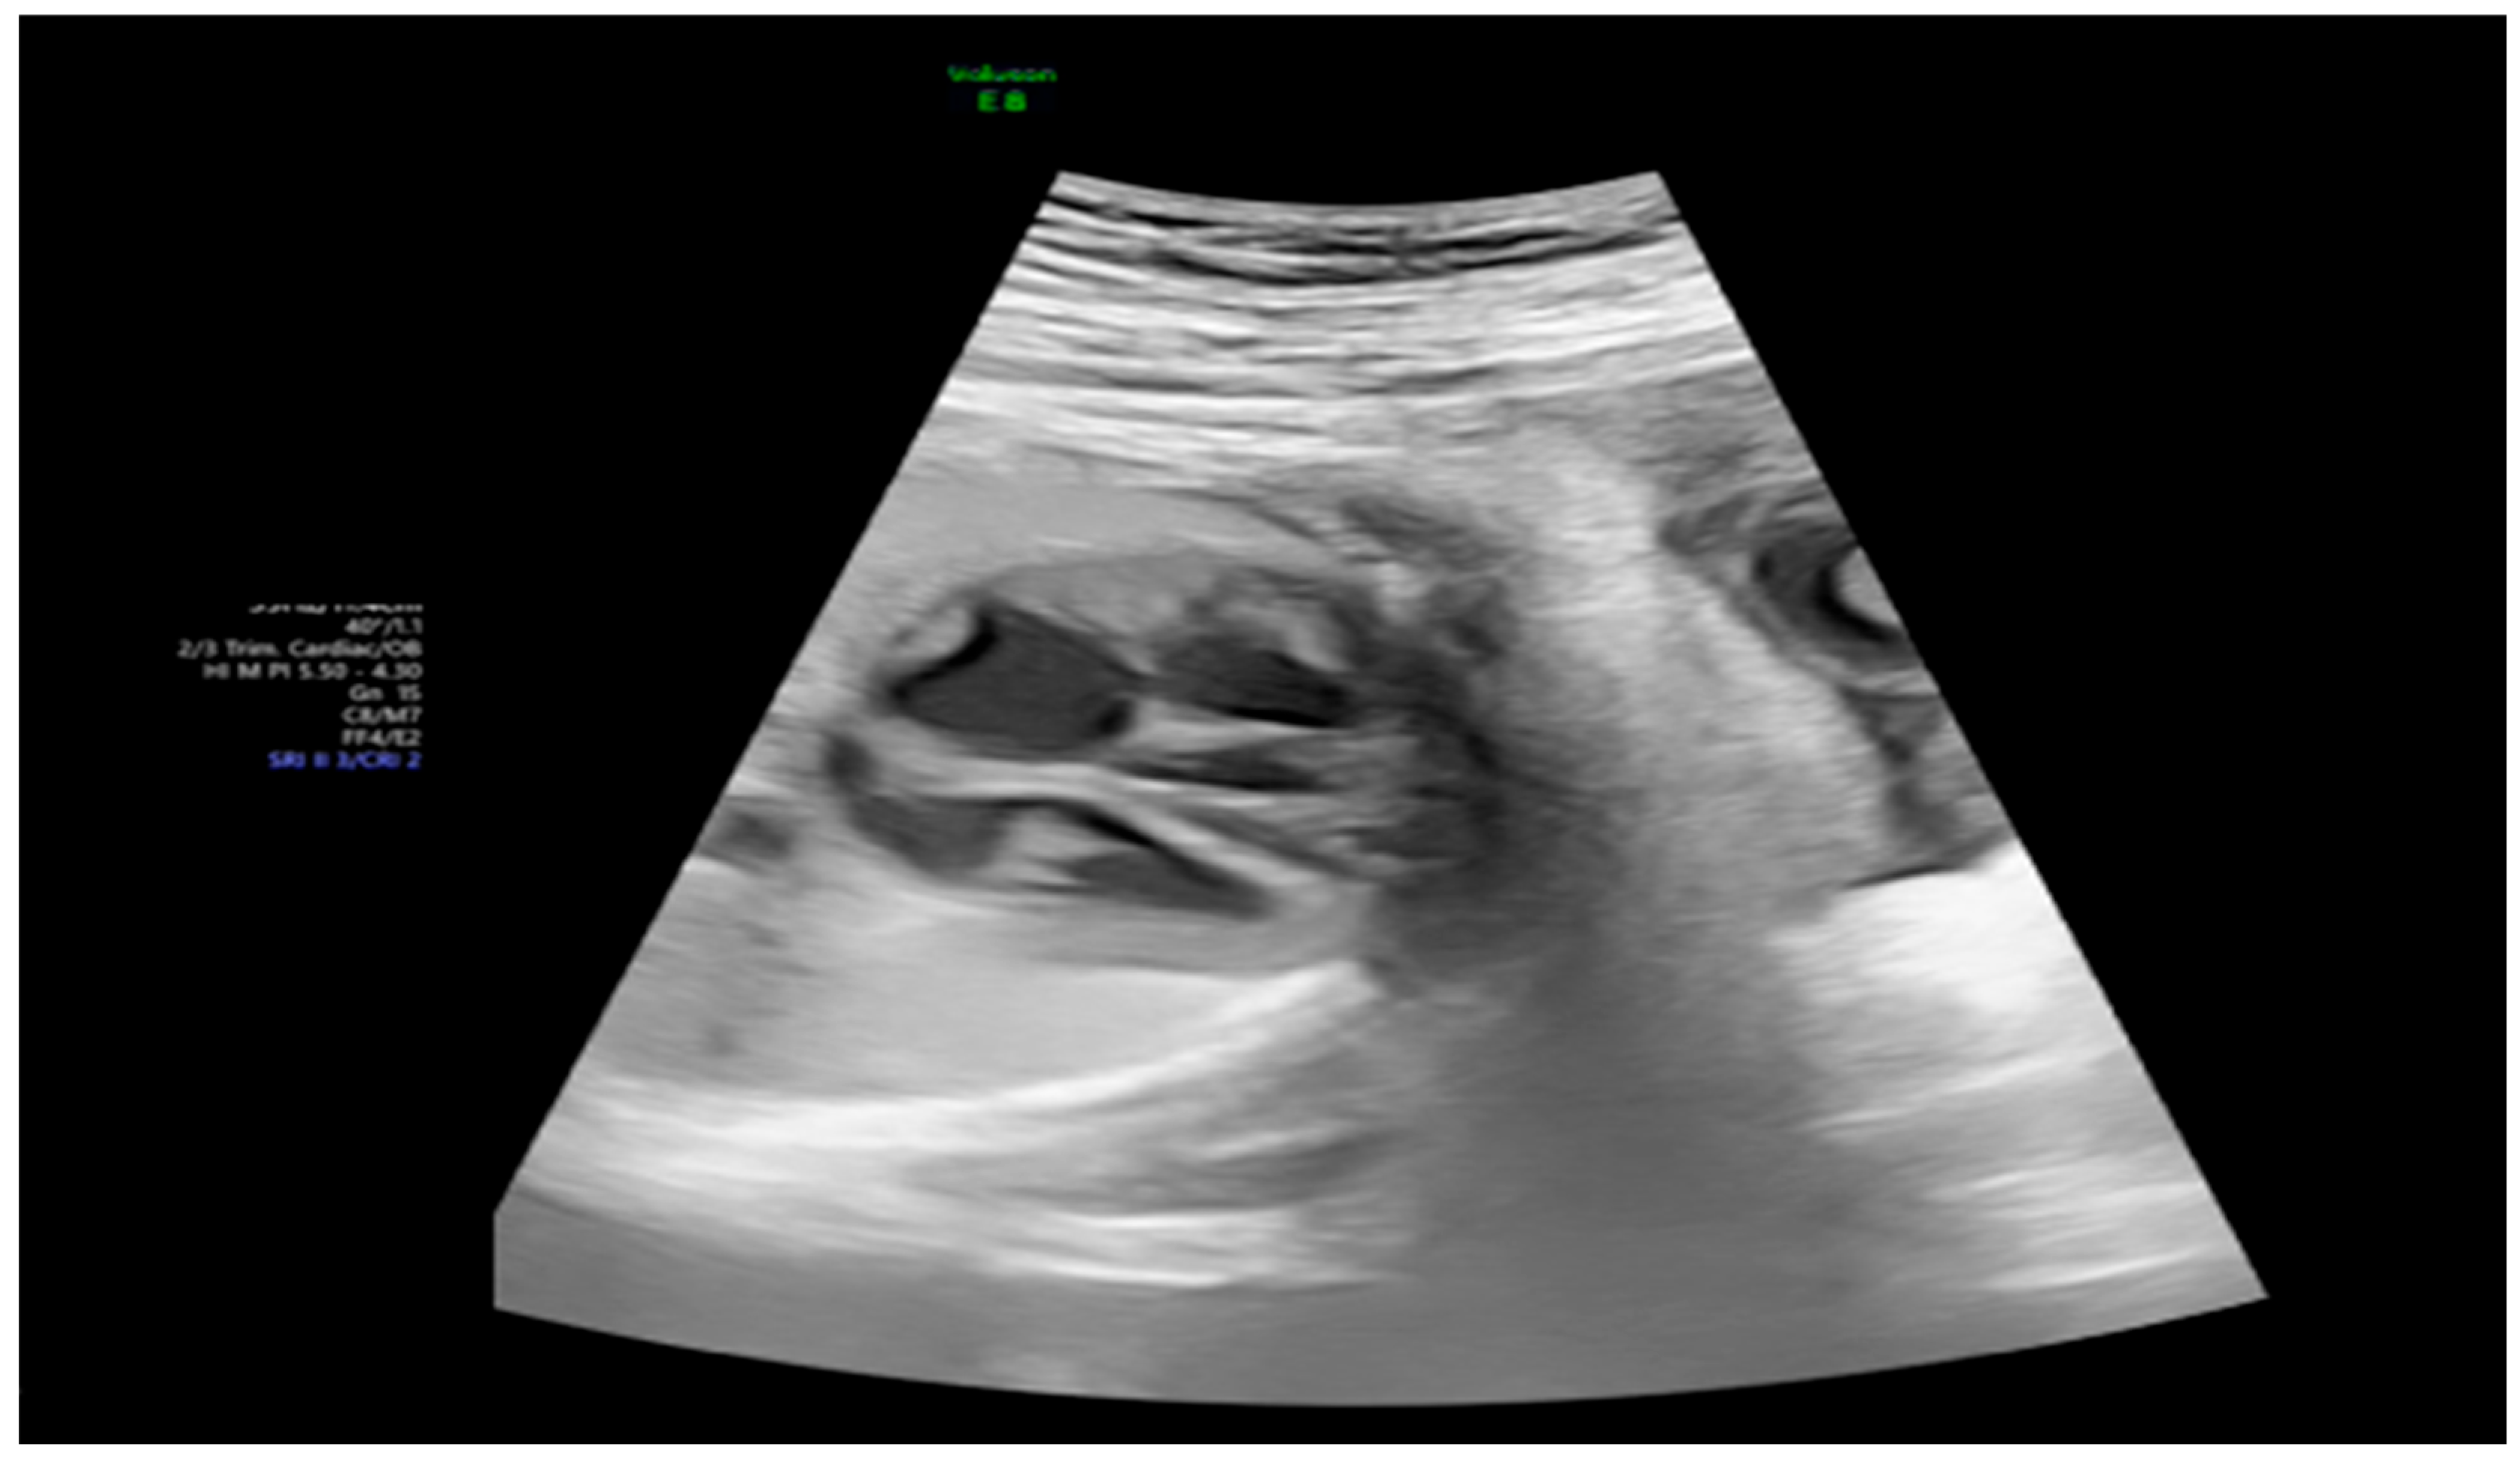

| 26 + 0 | Start of dexamethasone 4 mg/day | 60 | SF increased from 34% to 47%, but qualitative contractility decreased | Mild edema; no beta- agonists used |

| 28 + 0 | First IVIG cycle (65 g total) | 75 | SF increased to 52%; mild improvement in contractility | Initiated due to signs of fibroelastosis |

| 31 + 2 | Post-IVIG peak response | 70 | SF: 59% (LV), 52% (RV); marked biventricular improvement | Aortic isthmus 3 mm (Z-score –1.65) |